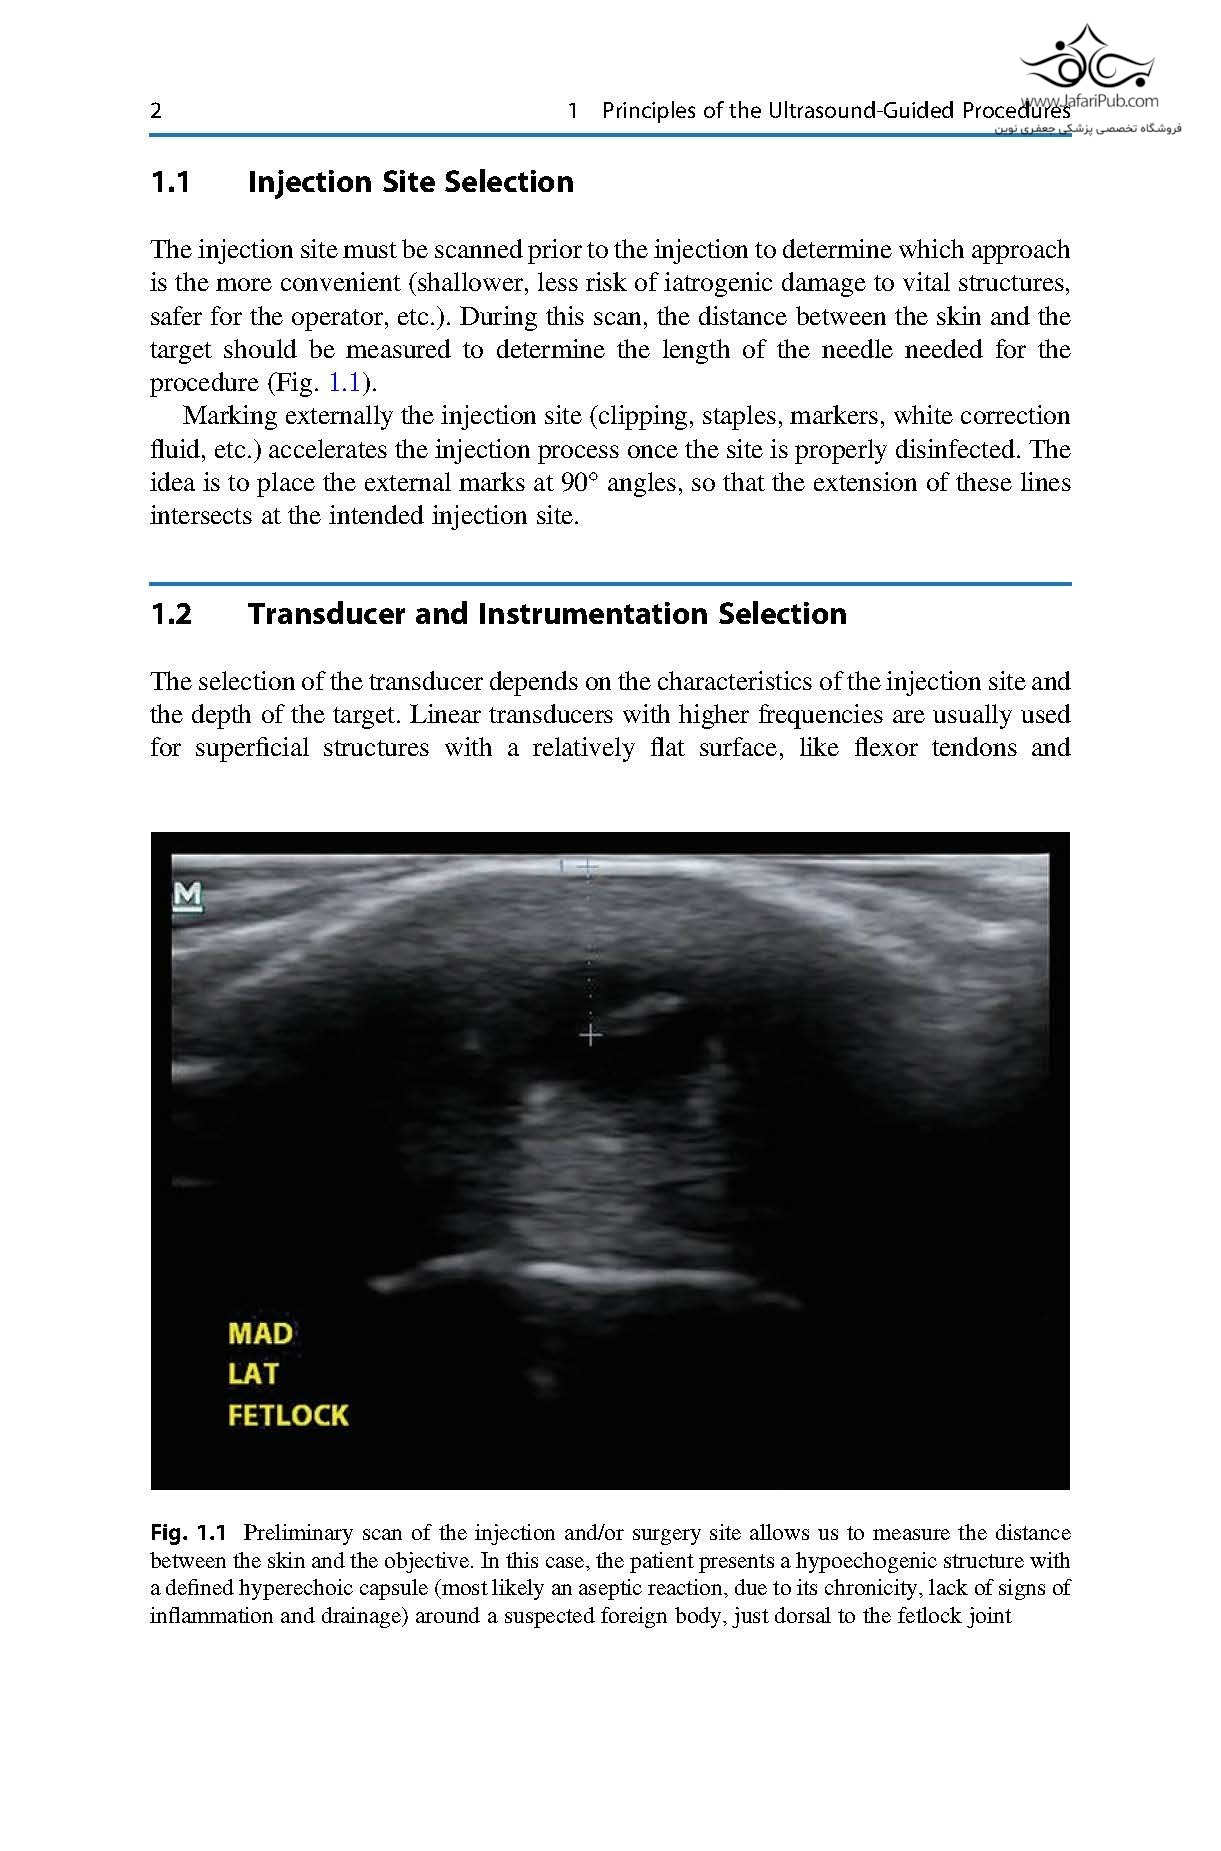

This book serves as a practical guide for equine veterinarians in orthopedics and surgery. It reviews and summarizes the current scientific evidence of the most commonly performed ultrasound-guided procedures for ultrasound-assisted surgery and injections.

For the first time, different techniques are compiled and richly illustrated with pictures and videos to guide the practitioner step-by-step. An initial discussion about the general principles of ultrasound-guided procedures sets the bases for clinicians to understand the general technique and apply it to each approach. Additional chapters describe the most common ultrasound-guided injections in different anatomical structures as well as the surgical approaches that are aided or guided with ultrasound.